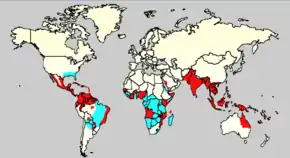

Es una infección muy extendida que se presenta en todas las regiones de clima tropical del planeta, y últimamente en regiones de clima templado con veranos cálidos y húmedos. En los últimos años la transmisión ha aumentado de manera predominante en zonas urbanas y se ha convertido en un importante problema de salud pública. En la actualidad, más de la mitad de la población mundial está en riesgo de contraer la enfermedad. La prevención y el control del dengue dependen exclusivamente de las medidas eficaces de lucha contra el vector transmisor, el mosquito.[4]

El número de casos de dengue ha aumentado dramáticamente desde la década de 1960. De acuerdo con la OMS, en las últimas dos décadas aumentó 8 veces más el número de casos notificados, con una estimación de entre 284 y 528 millones de personas infectadas anualmente.[5] Las primeras descripciones datan de 1779 y su causa viral y la transmisión fueron entendidas a principios del siglo XX. El dengue se ha convertido en un problema mundial desde la Segunda Guerra Mundial y es endémica en más de 110 países. Aparte de la eliminación de los mosquitos, se está trabajando en una vacuna contra el dengue, así como la medicación dirigida directamente al virus.

Epidemiología

La Organización Mundial de la Salud (OMS) estima que el número de afectados por dengue se encuentra entre los 100 millones y los 400 millones de personas cada año, con un total de medio millón que necesitan atención hospitalaria por presentar una forma grave de la enfermedad, con una mortalidad del 2,5 %.[cita requerida]

El dengue posee una extensión geográfica similar a la de la malaria (en países tropicales y subtropicales) pero a diferencia de esta, el dengue se encuentra en zonas urbanas.

El dengue se transmite a los humanos por el mosquito Aedes aegypti, el cual es el principal vector de la enfermedad en el hemisferio occidental, aunque también es transmitido por el Aedes albopictus.

Durante los años 2000, en Sudamérica se ha registrado el más dramático incremento de la incidencia del dengue, especialmente en Brasil, Colombia, Ecuador, Panamá Paraguay, Perú y Venezuela.[19]

Actualmente, en Venezuela se produce aproximadamente el 70 % de todos los casos en América, mientras que Colombia es donde se ha registrado el mayor número de casos de dengue hemorrágico y de casos fatales en los últimos años.[19]